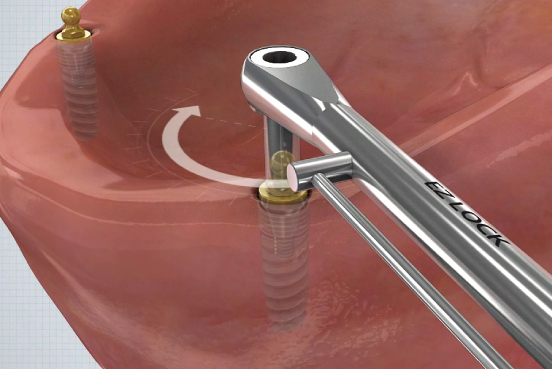

①

- 잇몸 높이에 맞는 EZ LOCK Abutment 체결▼

②

- EZ LOCK 전용드라이버를 이용하여 EZ LOCK 체결 (25N~)▼

③

- Plastic Carrier (EZ LOCK 전용 Impression Coping) 장착▼